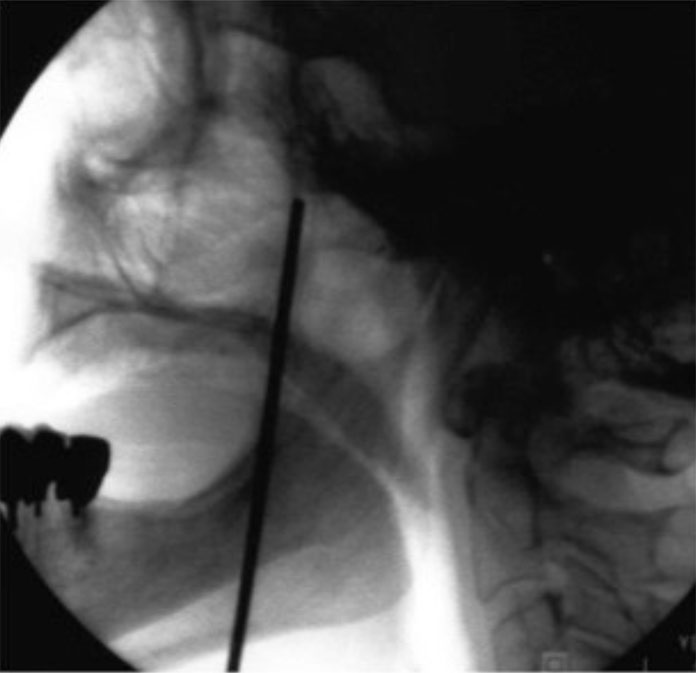

El paciente se coloca en decúbito supino. Con una proyección lateral del arco de rayos se localiza el angulo mandibular, de manera que podamos obtener una proyección lateral pura, se elimina el doble contorno mandibular, una vez conseguida esta proyección también se elimina la posibilidad de visualizar dos fosas en la proyección. En este momento se procede a fijar la cabeza del enfermo a la mesa quirúrgica. Con la proyección lateral se localiza la fosa pterigopalatina del lado a tratar En esta proyección se deben localizar la silla turca, el clivus y el seno esfenoidal. La fosa pterigoideapalatina se encuentra en la parte anteroinferior del seno esfenoidal, teniendo una forma de coma, situándose el ganglio en el tercio superior de la misma. Una vez localizada la imagen radiológica, se sitúa una varilla metálica que se superponga longitudinalmente con la fosa y se marca una línea en la piel que coincida con la barra. En el punto donde esta línea se cruza con el borde inferior del arco zigomático tendremos el punto de entrada. Se llega a la fosa a través de la escotadura mandibular y la fisura pterigomaxilar. Esta técnica no se puede realizar en visión túnel, pues se interpone el arco zigomático, por lo que tendremos que dirigir la aguja ligeramente superior y anterior, hasta que choquemos con hueso. A continuación recolocamos los rayos en visión anteroposterior comprobando la situación final de la aguja por dentro del borde de la fosa nasal, por encima del cornete medio.